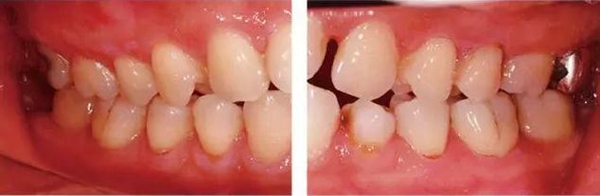

●參考病例① 35歲女性

35歲女性。妊娠4個(gè)月。過(guò)去雖然接受過(guò)刷牙指導(dǎo),但菌斑控制狀態(tài)依然不理想?;颊哂邪l(fā)現(xiàn)自己刷牙時(shí)牙齦出血。

●參考病例② 25歲女性

25歲女性。菌斑控制狀態(tài)不好。齦溝除磨牙處外全在3mm以下,X光照片上左上、右下、左下的第一磨牙上有垂直性骨吸收。這個(gè)病例是參考病例①10年前的狀態(tài),是典型的侵襲性牙周炎局部型。